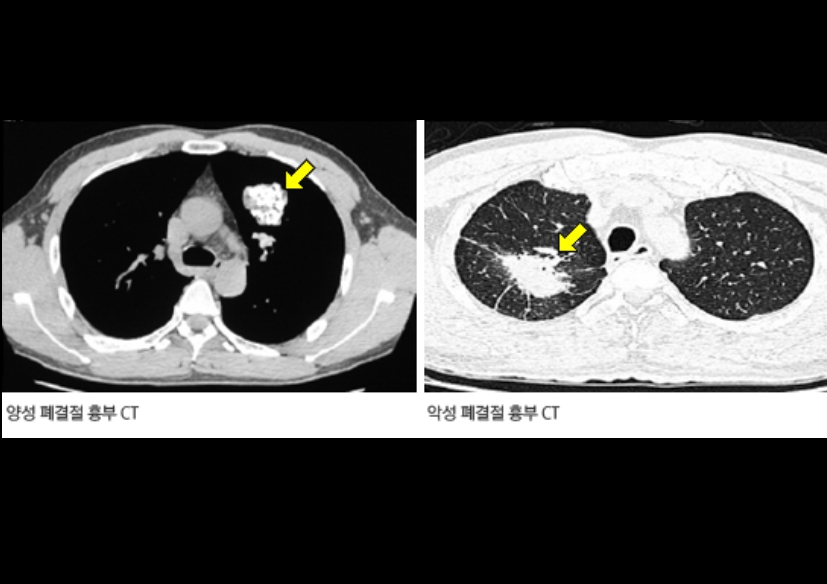

A. 꼭 그렇지는 않습니다. 결절이나 종양이 발견되더라도 크기, 모양, 경계, 주변 혈관과의 거리 등을 종합적으로 판단한 후 결정합니다. 크기가 작고 둥글며 경계가 뚜렷한 경우는 양성일 가능성이 높아 3~6개월 후 추적검사를 하기도 합니다. 그러나 비정상적인 모양이나 크기 변화가 빠른 경우에는 조직검사(생검)를 진행합니다.

Q8. 흉부CT 결과에서 ‘폐결절’이 나왔다는 말은 뭔가요?

A. 흉부ct로 볼수있는 질환 폐결절은 말 그대로 폐 안에 작은 혹이 있다는 뜻입니다. 대부분 양성(암이 아님)이고, 오래된 염증이나 석회화에 의한 것일 수도 있습니다. 그러나 결절의 크기가 8mm 이상이거나, 형태가 불규칙한 경우에는 추가 검사가 필요합니다. 영상의학과에서는 결절의 밀도, 경계, 주변 변화 등을 세밀하게 분석해 암 가능성을 판단합니다.